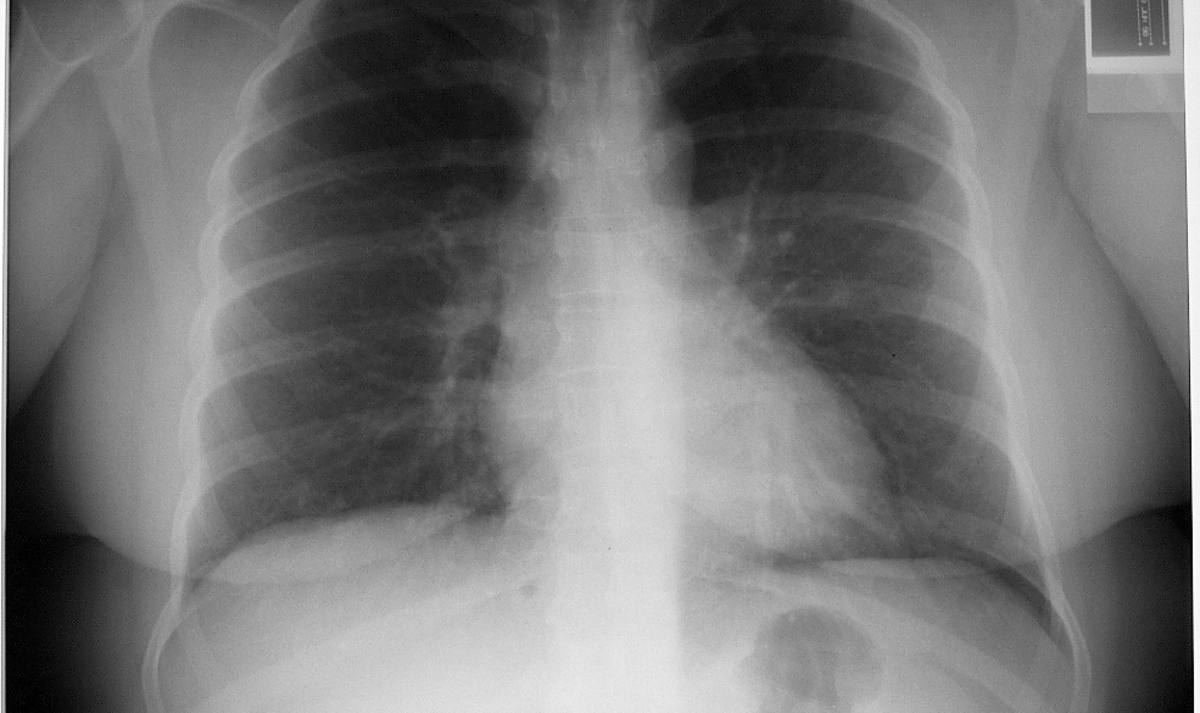

Chest Xray interpretation a structured approach Chest X Ray For Gallbladder These stones are formed from. Acute cholecystitis (ac) occurs as a result of inflammation of the gallbladder (gb) wall, usually because of obstruction of the cystic duct (see the image. There are several diagnostic tests used to determine gallbladder disease. Gallstone disease represents a group of conditions that are linked to, or caused by, gallstones. Persistent obstruction of the gallbladder. Chest X Ray For Gallbladder.